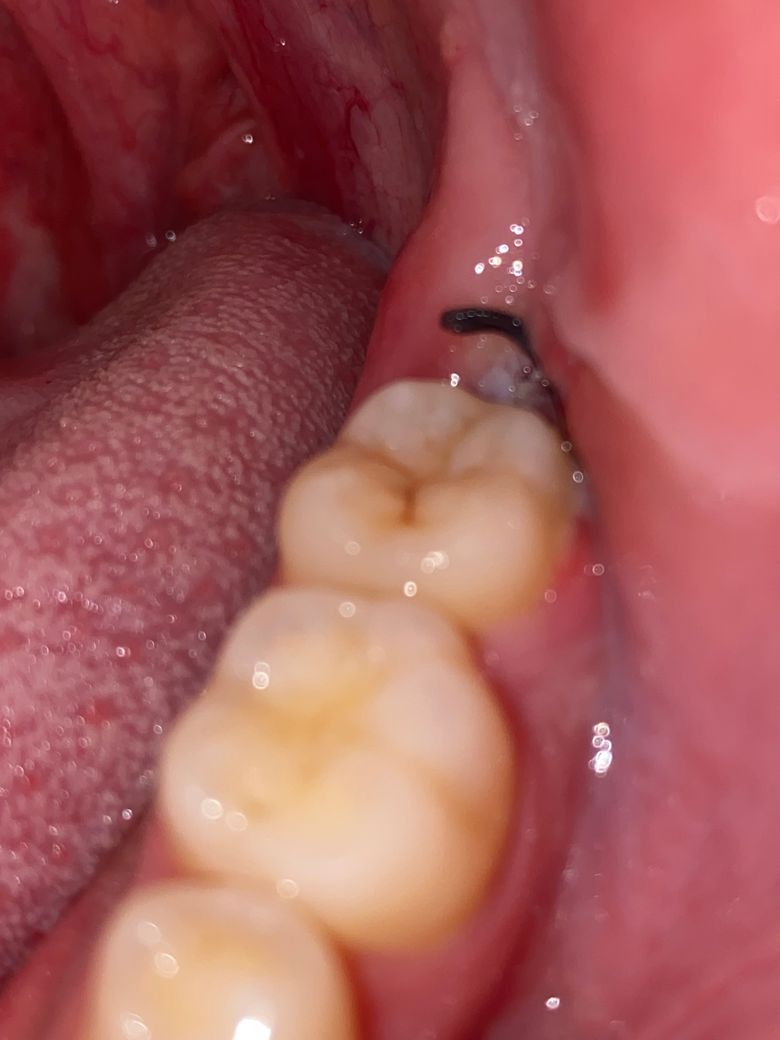

사랑니 발치 3일차인데 통증이 있습니다 드라이소켓인가요?

사랑니 발치한지3일차인데 쓰라리고 붓기와 불편한통증이 있습니다.

광대쪽도 아프네요

먹은거는 치킨정도 먹었는데 드라이소켓인가요?

• 1번 째 사진

사랑니 발치 부위가 사진상으로 아주 잘 보이지는 않지만 특별히 드라이소켓이 발생한 것으로 보여지는 양상은 아닙니다

사랑니 발치후 1주정도는 통증 및 붓기가 동반될수 있으며, 사진상 드라이 소켓으로 보이지는 않습니다. 통증이 있는 경우 소염진통제를 약국에서 구매하여 복용하면 불편감 경감에 도움이 됩니다.

드라이소켓은 아닌거 같습니다. 드라이소켓은 감염의 일종으로 냄새도 많이 나고 회색빛이 날꺼에요. 일단 약을 드시고 치과에 가셔서 소독한번 받으시면될것같습니다.

3일차면 붓기나 통증이 있을 수 있습니다. 드라이소켓은 견디기 힘든 정도의 통증이 나타납니다.

사진으로는 드라이 소켓인지 확인을 하기 힘듭니다.